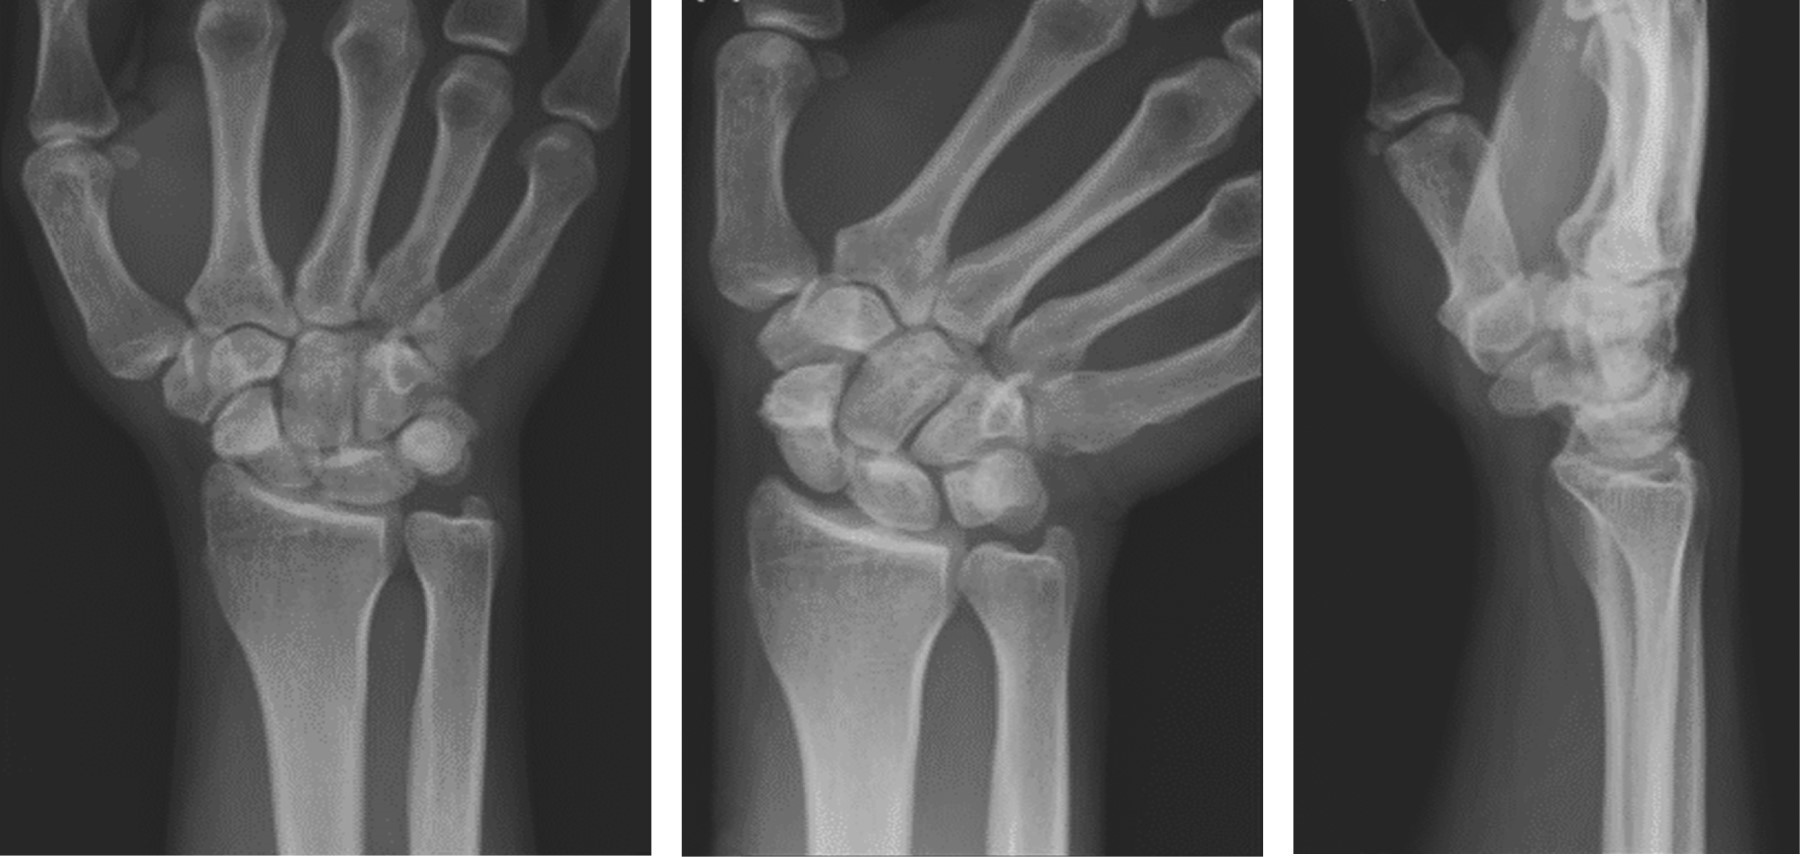

A 28-year-old right-handed male, with no comorbidities, sustained a wrist injury when he fell from his own height and landed with an outstretched right hand. He evolved with swelling, limitation of movement, and tenderness on palpation in his anatomical snuff box. He was initially assessed in another institution where through plain radiographs the diagnosis of scaphoid fracture was made. It was classified as a Herbert and Fischer type B2 (complete displaced scaphoid waist fracture) (Figure 1). Consequently, he was immobilized with a below-elbow cast without the inclusion of the proximal phalanx of the thumb. After three weeks, the patient removed his cast and decided to abandon the treatment and medical follow-up. At seven months he consulted again for pain. Once more, posteroanterior, lateral, and scaphoid (30° wrist extension, 20° ulnar deviation) plain radiographs of the wrist were requested (Figure 2). The fracture exhibited absence of consolidation. Due to the evolution time (more than six months from the initial trauma), a scaphoid nonunion was diagnosed. A CT scan was requested to assess displacement. This revealed a Herbert type D nonunion (established nonunion), with no density alteration in the scaphoid fragments and no displacement (Figure 3). According to the Slade and Geissler classification, it was a grade II nonunion, with no sclerosis, no bone cysts, and a small resorption edge. Surgical treatment was indicated, but the patient refused. Then he returned to our institution 10 months after the initial injury. He presented with pain in the anatomical snuffbox, on axial compression of the first metacarpal, and on palpation of the scaphoid tubercle. Mobility was similar to the contralateral side but painful (visual analogue scale [VAS] 7/10) (Table 1). Surgical treatment was once more indicated. The patient was then lost in follow-up and returned to control 15 months after the initial injury without having undergone any type of treatment or immobilization. He showed a spontaneous clinical improvement, a complete absence of pain (VAS 0/10) and range of motion, and grip strength similar to the healthy contralateral side (Table 1). Plain radiographs and CT scan with 3D reconstruction were requested. The new images showed scaphoid consolidation (Figures 4 and 5).

In our case, surgical treatment was proposed when assessing the initial fracture displacement as well when it evolved to nonunion. Afterwards spontaneous consolidation was confirmed by a clinical improvement and consolidation signs in radiography and tomography images, as proposed by Hannemann et al.15

Figure 4

Figure 5